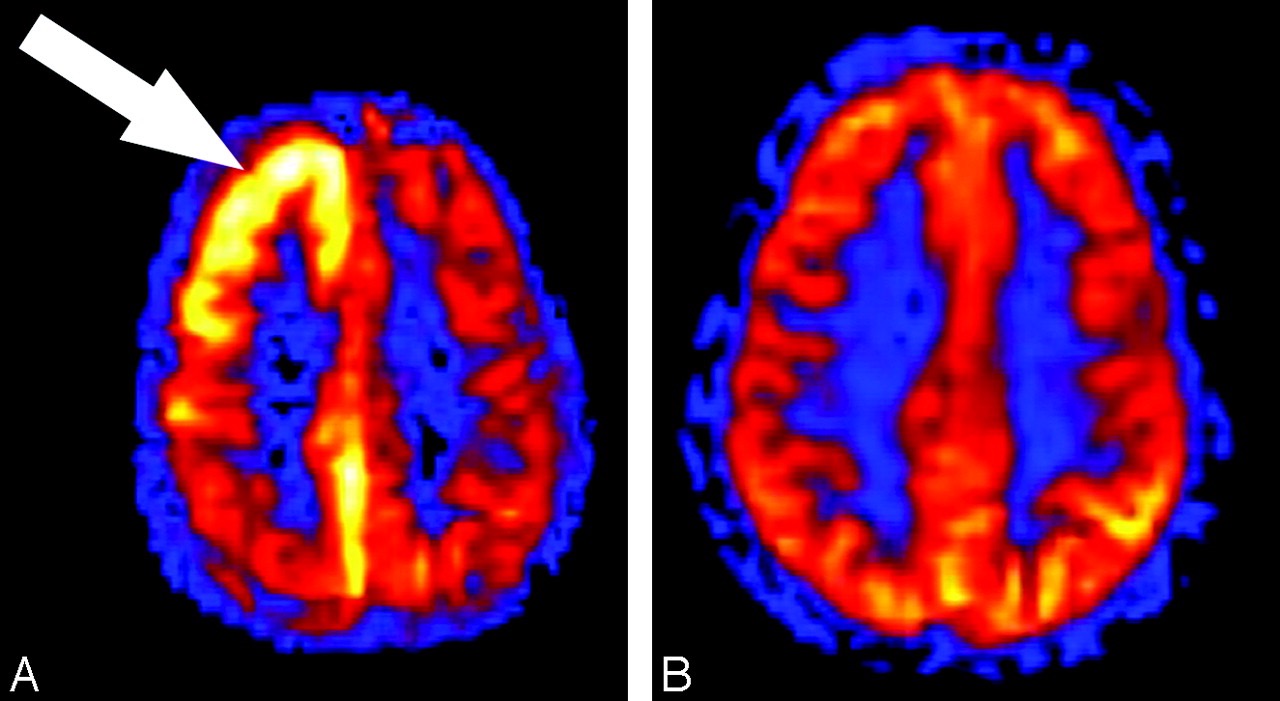

As we continue to unravel the basis for this link, perhaps from an ocular perfusion standpoint, it is an important reminder for us to maintain a multifactorial approach in managing patients with migraines and others at risk for glaucoma.